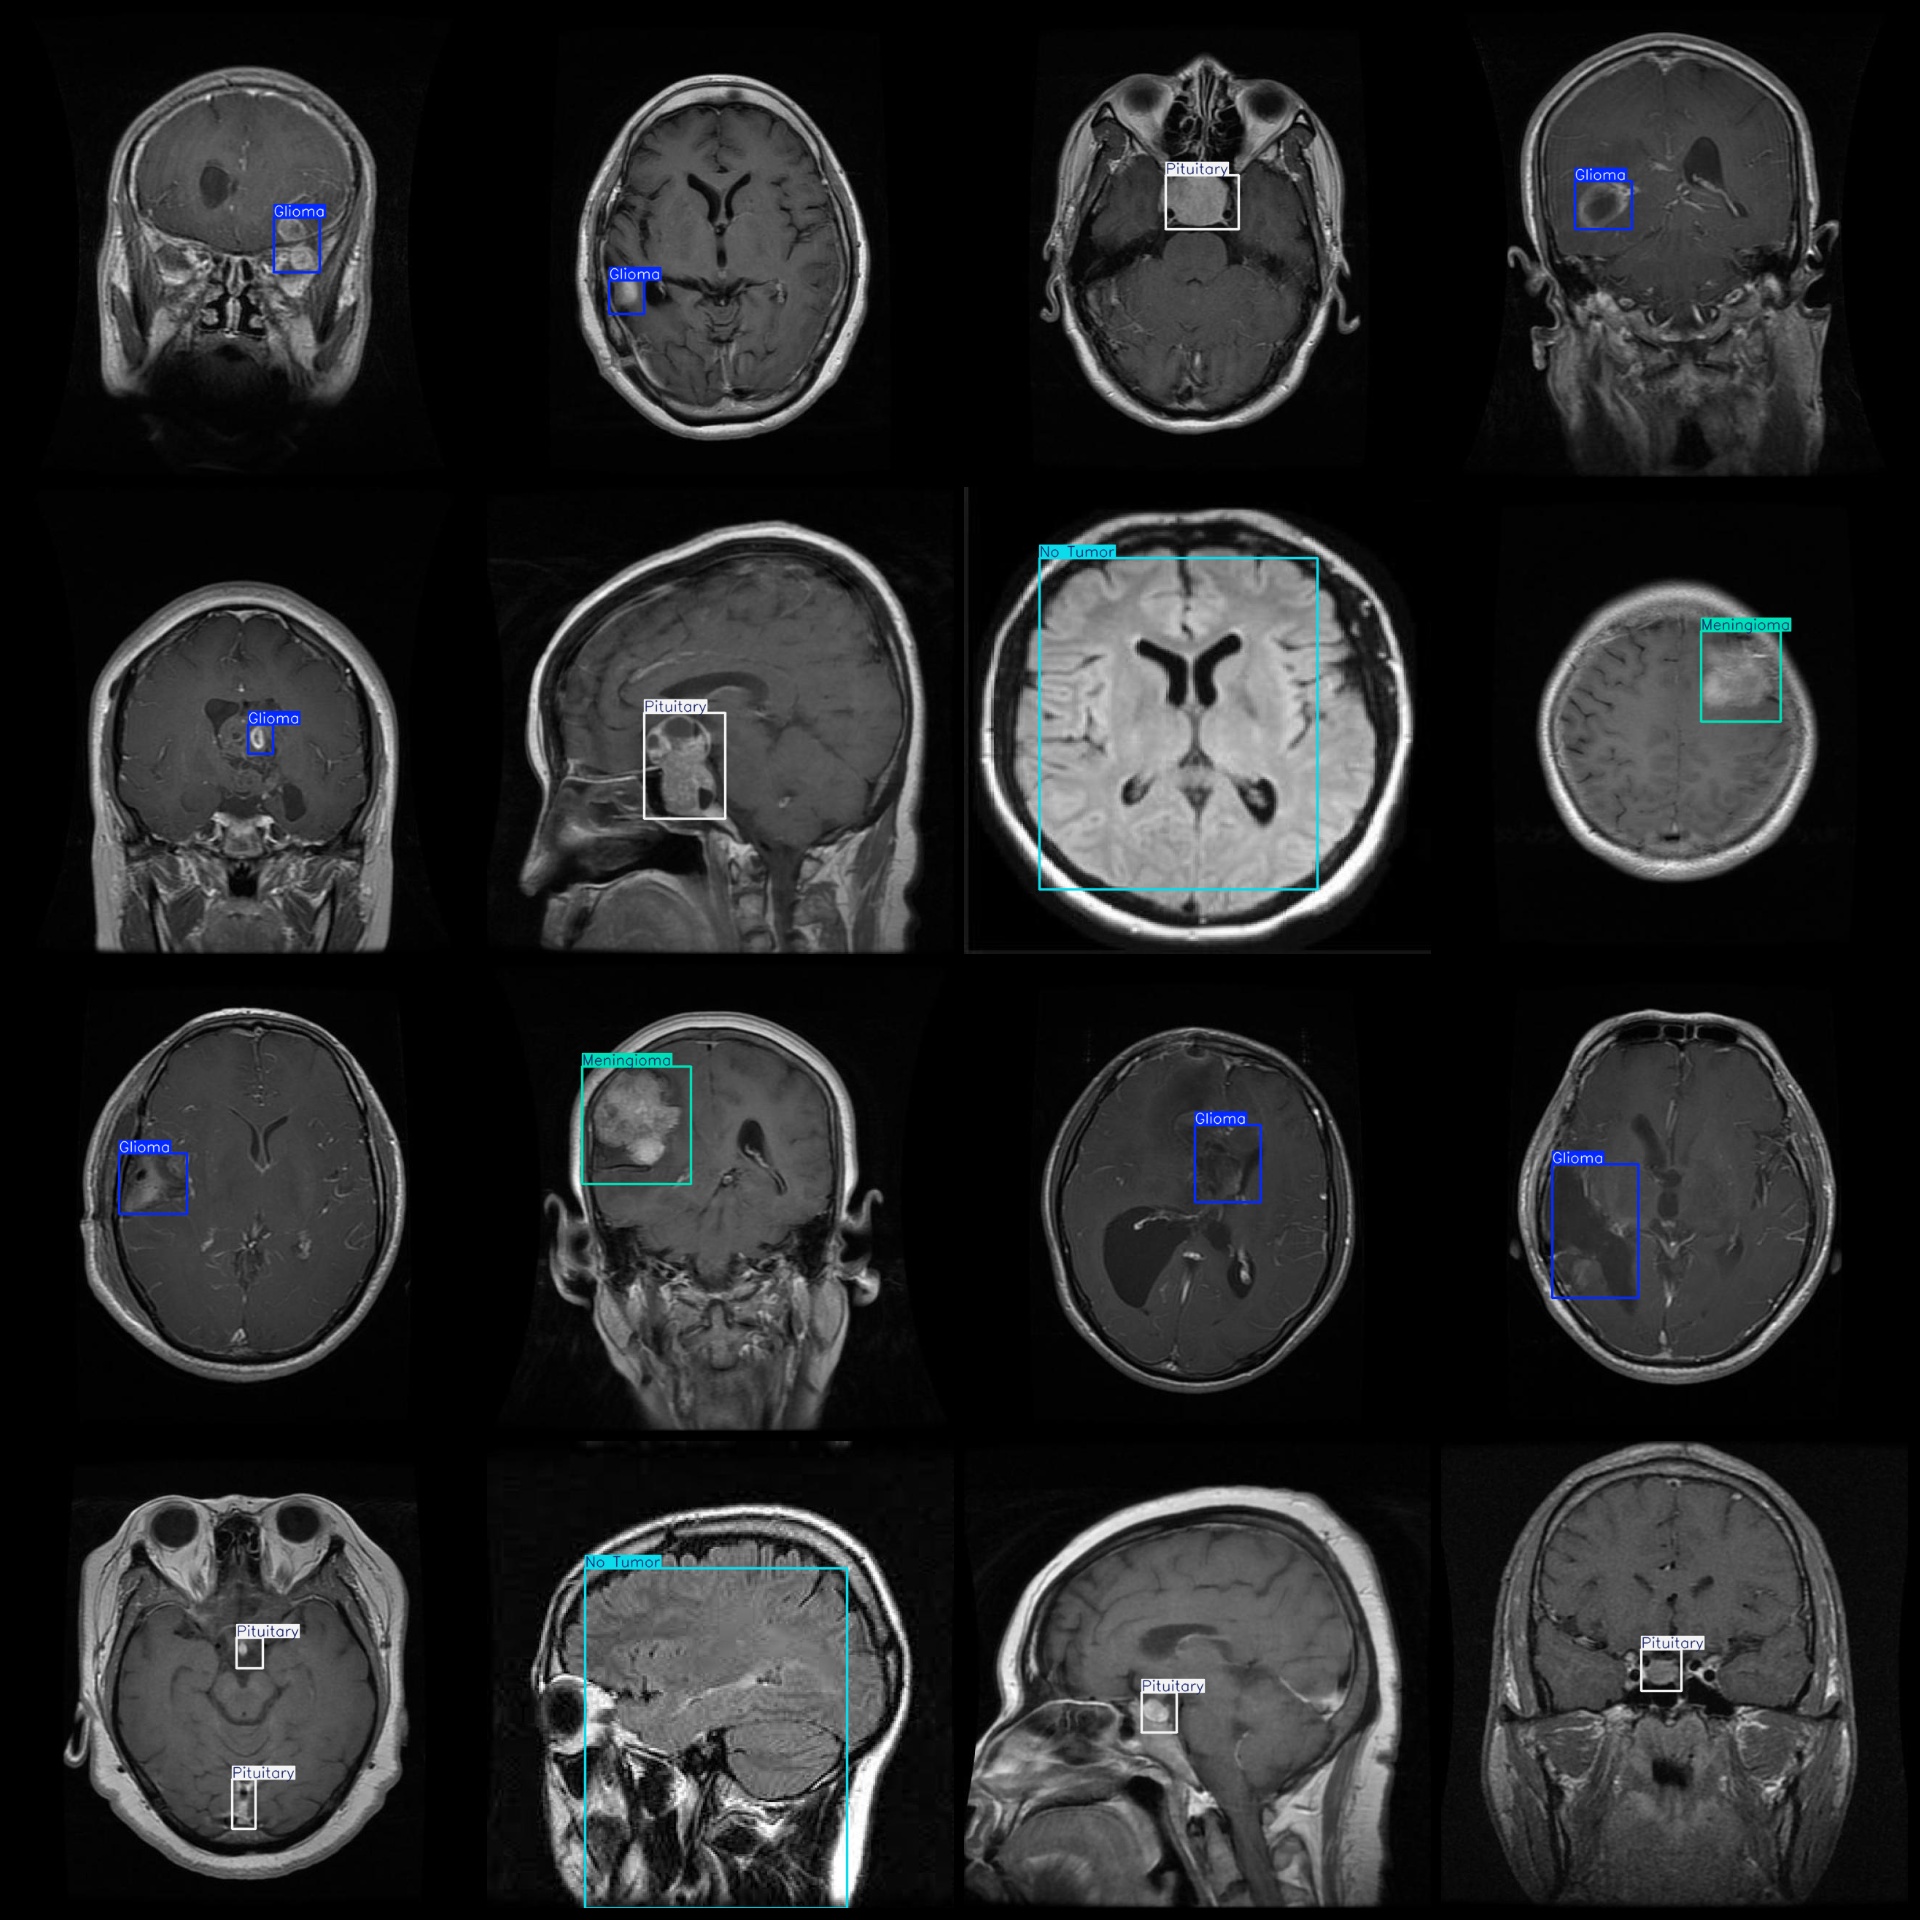

标注类别名称(注意yolo格式类别顺序不和这个对应,而以labels文件夹classes.txt为准):["Glioma","Meningioma","No Tumor","Pituitary"]

每个类别标注的框数:

Glioma (胶质瘤) 框数 = 830

Meningioma (脑膜瘤) 框数 = 547

No Tumor (无肿瘤) 框数 = 483

Pituitary (垂体瘤) 框数 = 612

总框数:2472

标注例子: